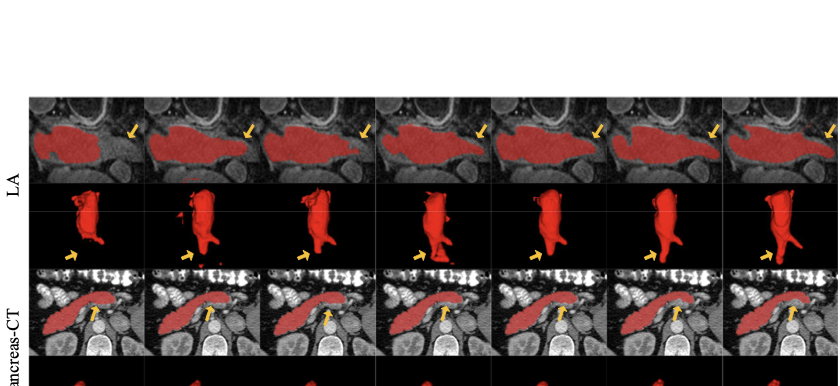

Table [tab:LA_result_table] presents a comparison of our method with other state-of-the-art approaches on the LA dataset. We evaluate our method on the V-Net using 10% and 20% labeled data as well as fully supervised data. With only 10% labeled data at hand, our model exhibits noteworthy enhancements over DTC . Specifically, we achieve improvements of 2.11% and 3.16% in Dice and Jaccard scores, respectively. When 20% labeled data is available, our method achieves a 1.70% improvement in Dice and a 2.81% improvement in Jaccard compared to MC-Net+. Notably, our approach even outperforms the fully supervised results obtained on V-Net. Based on the visualizations in Fig. 6, the first and second rows demonstrate that with only 20% labeled data, other baseline models exhibit fragmentation or missing portions in the challenging areas. In contrast, our method achieves comprehensive segmentation in these challenging regions.

Performance on Pancreas-CT Dataset

Table [tab:Pancreas_result_table] presents a comparison of our method with other state-of-the-art techniques on the Pancreas-CT dataset. When the labeled data is limited to only 10%, SASNet achieves significant improvements compared to other methods. Specifically, our method outperforms URPC in Dice score by 2.85% and in Jaccard by 3.40%. As the percentage of labeled data increased to 20%, our method outperforms URPC in Dice score by 1.58% and in Jaccard score by 2.09%. The third and fourth rows of Fig. 6 illustrate the visual results on the Pancreas-CT dataset with 20% labeled data, other methods tend to misclassify background as foreground. In contrast, our method effectively addresses this issue and accurately segments the target.